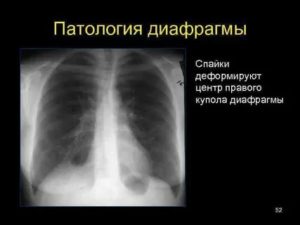

Прямым признаком, указывающим на наличие спайки, являются тени, которые видны на рентгене. При этом она не меняется во время выдоха и вдоха больного. Также будет снижена прозрачность легочного поля. Возможны деформации грудной клетки и диафрагмы. Кроме того, диафрагма может быть ограничена в подвижности. Чаще всего такие спайки располагаются в нижней части легкого.

Основным признаком спаечного процесса на легком является наличие тени, которая появилась на снимке. Стоит учесть тот факт, что она никак не изменяет свою форму при вдохе и выдохе. Наряду с этим легочное поле будет менее прозрачным, а диафрагма и грудная клетка могут быть несколько деформированы. Зачастую спайки наблюдаются внизу легкого.